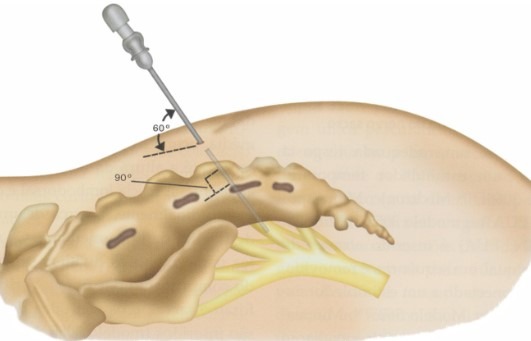

تحریک عصب ساکرال (Sacral Nerve Stimulation) یک روش درمانی نوین است که با ارسال پالسهای الکتریکی به عصبهای ساکرال (S2-S4)، عملکرد عضلات مقعد، روده و مثانه را بهبود میبخشد. این روش شامل:

- قرار دادن یک الکترود در نزدیکی عصب ساکرال

- تست اولیه: یک الکترود موقت در نزدیکی عصب ساکرال قرار میگیرد تا پاسخ بیمار به درمان ارزیابی شود.